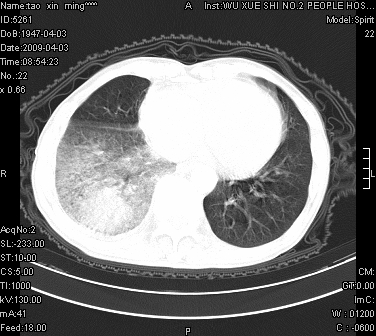

男.62.咯血.胸痛

是不是外伤的,看起来右侧肋骨骨折,右肺唑伤,右胸腔积血, 右肺背段可见一软组织肿块,边缘清晰,可以和中中央型肺ca合并

肺出血,周围型肺癌,右侧胸腔积液

右下周围型肺癌,右下肺出血,右侧胸腔积。

1)考虑右肺下叶周围型肺癌,并右肺下叶肺出血。2)右侧少量胸腔积液。

1)考虑右肺下叶周围型肺癌。2)右侧少量胸腔积液。

右下肺阴影,右胸腔少量积液。